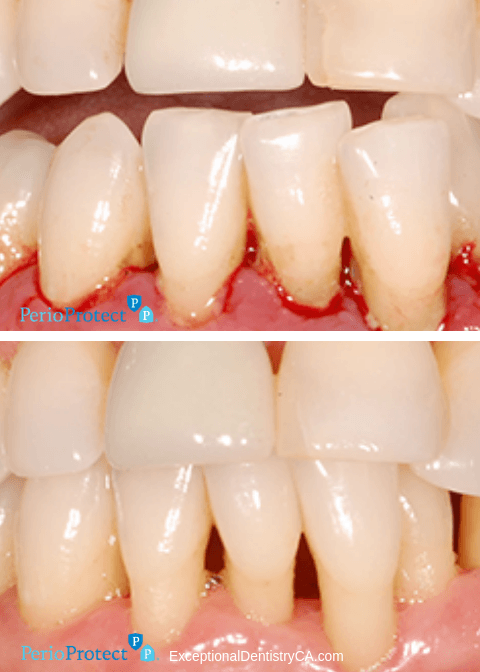

The Perio Protect Method was devised as a way to treat gum infections without surgery and with results. It resolves infection while reducing gum disease-causing bacteria, making way for long-lasting results. Treating gum disease with the Perio Protect Method has been shown to reduce the presence of the most damaging pathogens in your gums by up to 90%. Gum disease treatment helps reduce the risk of heart disease, type 2 diabetes, respiratory disease, Alzheimers disease, colorectal cancer and pre-term births and low birth-weight babies.

Studies have traced pathogens that lead to gum disease to the same pathogens known to cause other systemic inflammation and illness. Perio Protect is designed to reach the places where bacteria thrive below the gumline, in your periodontal pockets. Perio Protect involves a patented prescription antimicrobial medication that helps kill those pathogens and remove bacteria and plaque in periodontal pockets, where brushing, flossing and even mouth wash cannot reach. The antimicrobial medication also helps whiten teeth and freshen breath.

Call our team today and schedule your reservation to experience fresher breath, whiter teeth and a healthier mouth and body with Perio Protect!